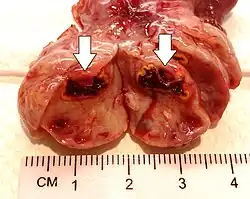

This type of functional cyst occurs after an egg has been released from a follicle. The follicle then becomes a secretory gland that is known as the corpus luteum. The ruptured follicle begins producing large quantities of estrogen and progesterone in preparation for conception. If a pregnancy doesn't occur, the corpus luteum usually breaks down and disappears. It may, however, fill with fluid or blood, causing the corpus luteum to expand into a cyst, and stay in the ovary. Usually, this cyst is on only one side, and does not produce any symptoms.[1][2]

A ruptured corpus luteum can cause hemoperitoneum with abdominal pain, and is a common condition in women of reproductive age. It may be confused with ectopic pregnancy.[4]